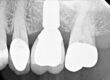

Preop radiograph from the general dentist. We do not have the exact date for this image, but I believe it was taken prior to any recovery attempts. Note the fragment position is above the first implant thread, as viewed in the right cropped image. Green arrow is the top of the implant threading, the yellow arrow is the top of the screw fragment. A Type I or II case in our fractured screw algorithm.